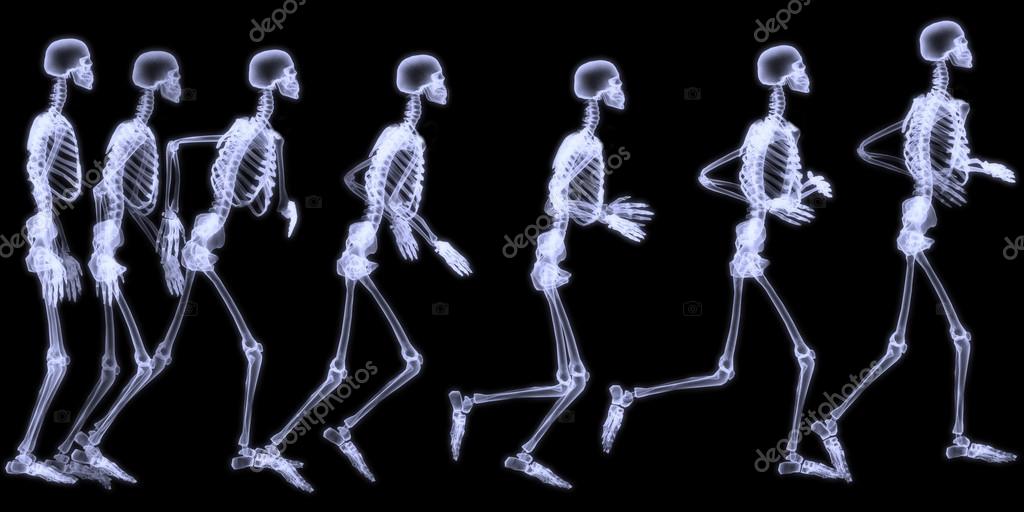

If you are looking for Anatomía de rayos x y cuerpo humano | Foto Premium you've visit to the right page. We have 35 Pics about Anatomía de rayos x y cuerpo humano | Foto Premium like Yoga, nuestro cuerpo y rayos X – Un Poco Geek, 27,201 fotos de Cuerpo humano rayos x - Fotos, imágenes y otros and also Radiografía de rayos X del cuerpo humano (esqueleto)) 2023. Read more:

Anatomía del cuerpo humano en vista de rayos x representación 3d. Cuerpo humano de rayos x con piel transparente representación. La imagen de rayos x del cuerpo humano fotografía de stock